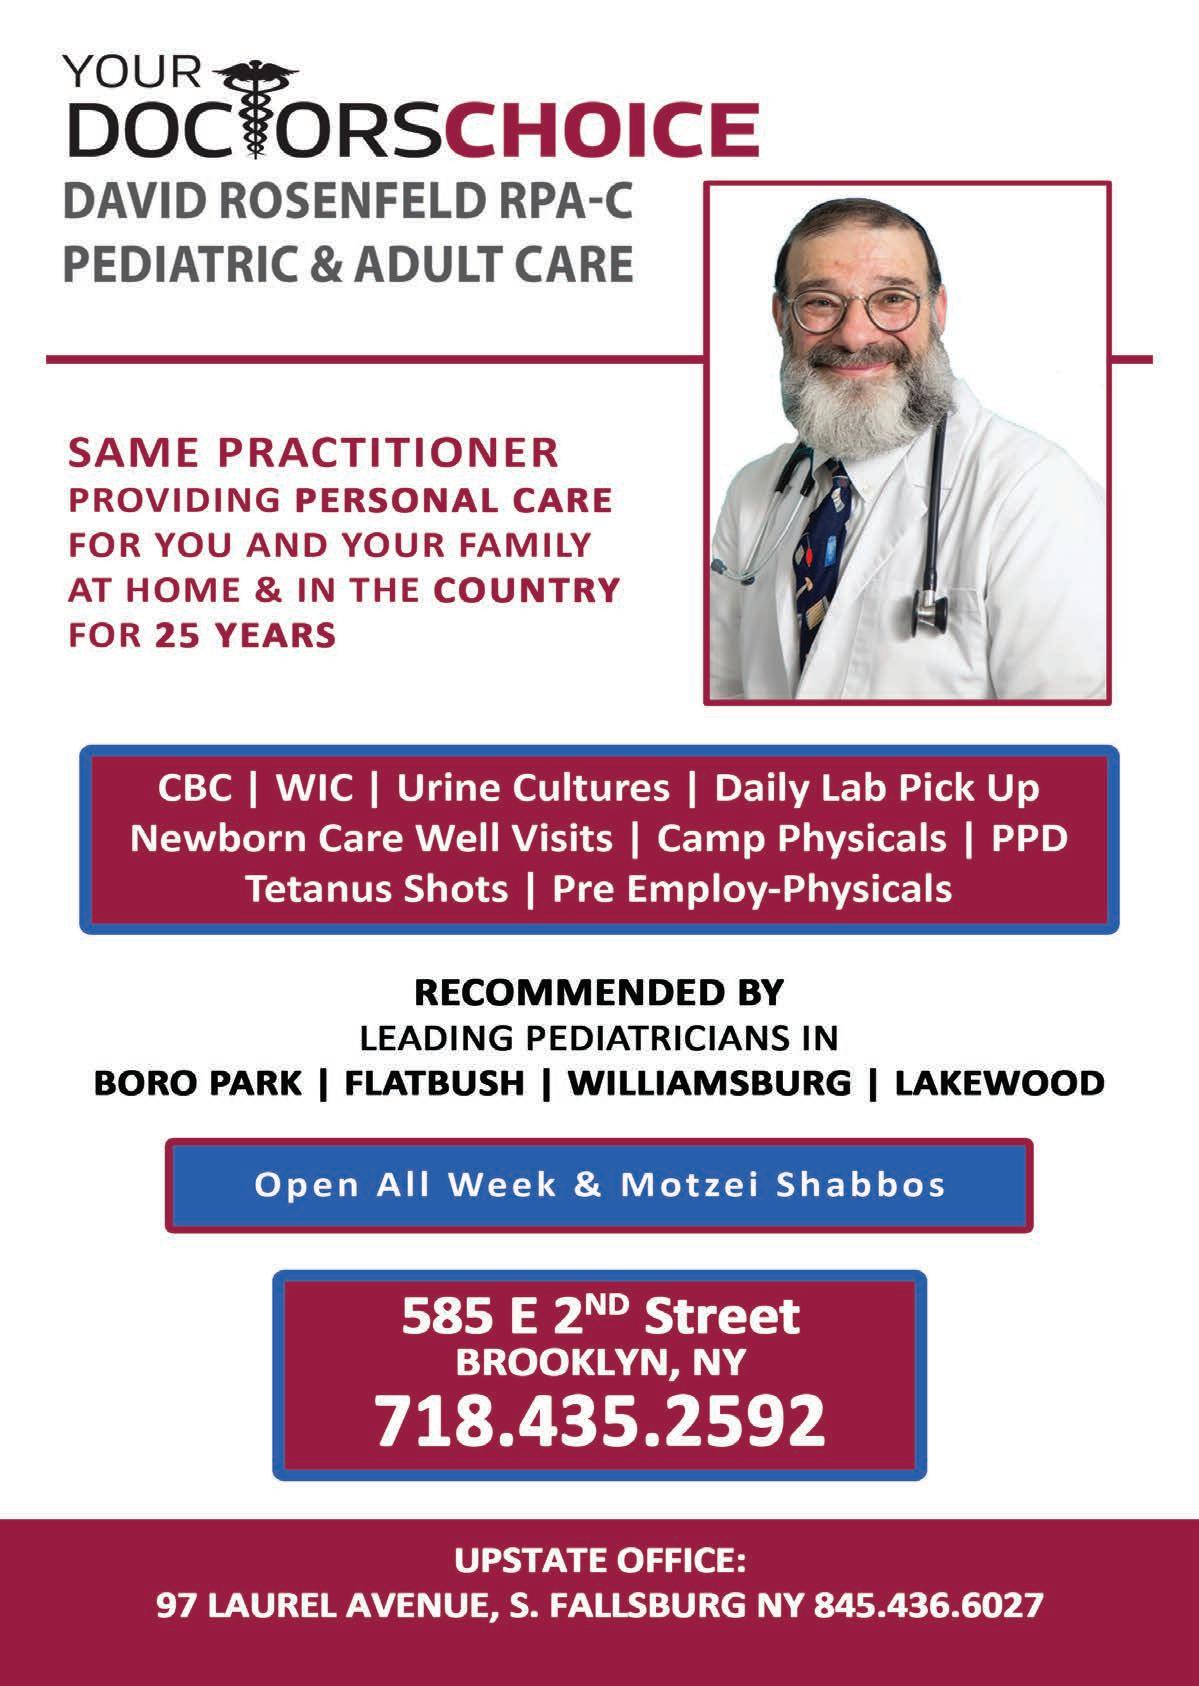

Call now to ensure that one of our 8 mobiles will visit your camp or colony this summer. 845.354.9300 #1049 Summertimes@refuahhealth.org SOUTH FALLSBURG 36 LAUREL AVE. SOUTH FALLSBURG, NY LIBERTY 1885 NY-52 LIBERTY, NY 12754 REFUAHHEALTH.ORG EXCITING NEWS FOR NJ RESIDENTS! WE NOW ACCEPT NJ INSURANCE choose quality care, that comes all the way to you.